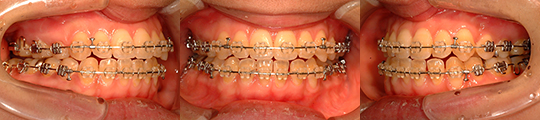

| 治療タイプ | 顎変形症 (保険診療) |

| 性別 | 女性 |

| 治療開始時年齢 | 27才10か月 |

| 診断名 | 他院での矯正治療の既往がある 上顎咬合平面の右上がり傾斜と 下顎骨右方偏位を呈する 開咬を伴う顔面非対称 |

| 使用装置 | 上下顎マルチブラケット矯正装置 |

| 抜歯or非抜歯 | 非抜歯 |

| 抜歯部位 | 上顎右側:(第一小臼歯既抜) 下顎右側:(第三大臼歯) 下顎左側:(第一小臼歯既抜) |

| 顎矯正手術術式 | 術前矯正治療を行わずに、 上顎Le Fort T型骨切り術 (LF-T : Le Fort T osteotomy) 両側下顎枝垂直骨切り術 (IVRO : Intraoral vertical ramus osteotomy) |

| 手術時年齢 | 27才10か月 |

| 治療期間 | 術前矯正治療を行わずに、 1年4か月(マルチブラケット装置装着期間) 装置装着1か月後に手術 術後1か月半より治療開始 |